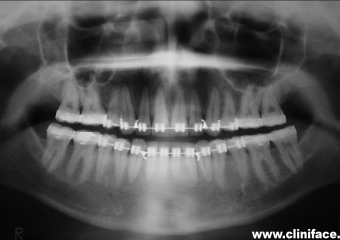

Raio x panorâmico inicial

Raio x panorâmico final